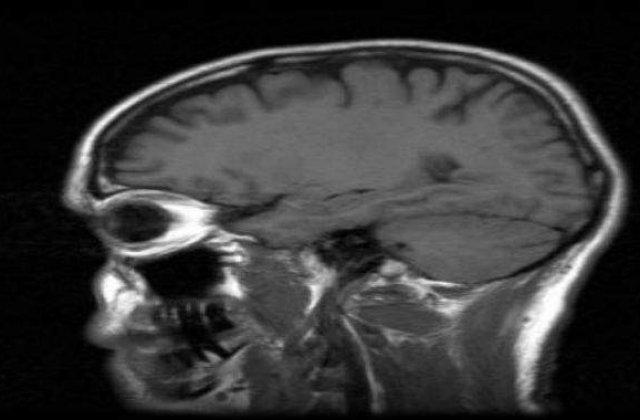

Voluntarii au privit fotografii cu partenerii lor de viata si au fost rugati sa se gandeasca la acestia atunci cand creierele lor erau analizate la tomograf.

Daca imaginile cu creierele voluntarilor prezentau o activitate mai mare in nucleul caudat - zona asociata cu reactiile emotionale la frumusetea vizuala -, dar o activitate mai scazuta in cortexul orbitofrontal medial - zona asociata cu criticile si cu judecata -, atunci relatia celor doi avea sanse mari sa reziste in timp.

In mod surprinzator, centrii asociati placerii erau mai putin activi in creierele cuplurilor care locuiau impreuna.

Oamenii de stiinta spun ca activitatea cerebrala redusa din aceasta zona, ce are o legatura cu dependenta si cu recompensarea, a fost asociata cu satietatea si cu satisfactia.